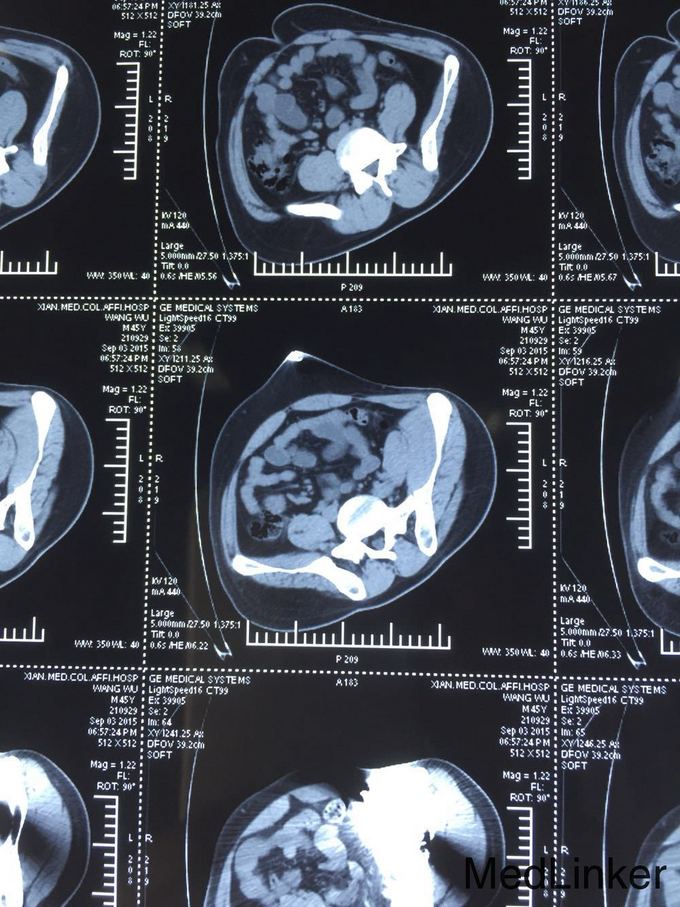

查体:T:36.6℃,P:80次/分,R:19次/分,Bp:130/85mmHg。心肺未见明显异常,腹平坦,无腹壁静脉曲张,腹部柔软,无压痛、反跳痛,腹部无包块,左侧腰髂部近左臀部可见钢筋样异物刺入直达左下腹腹壁皮下,未穿透腹壁皮肤,左臀部皮肤裂伤伴出血,伤口处压痛,肝脾肋下未触及,左下腹压痛,Murphy氏征阴性,移动性浊音阴性,肝脾肾区无叩击痛,肠鸣音未见异常。 辅助检查:全腹部CT检查示:1.盆腔见条状金属致密物,从左臀穿向前下腹部皮下,长约28cm;2.左侧腹膜周围见少许渗出性改变;3.左侧精索肿胀,其内气体影,左侧睾丸肿胀;4.左侧髂骨骨折。